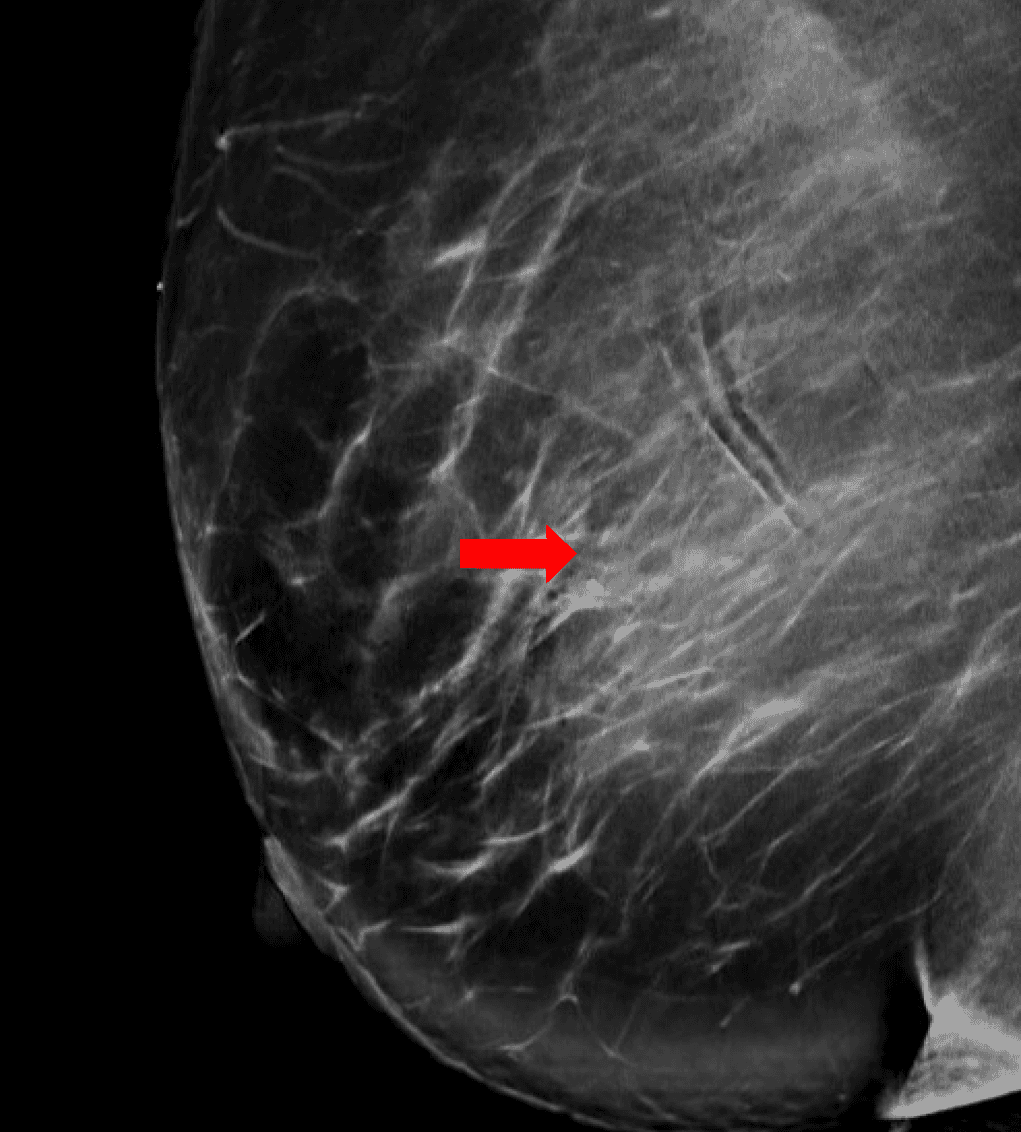

Patient is a 46-year-old premenopausal female with no other contributing past medical or surgical history who presented initially to the breast surgery clinic after her annual screening mammogram discovered a nonpalpable right breast mass measuring 0.6 x 0.8 x 0.7 cm at 11 o’clock (oc), 1 cm from the nipple (FTN) (Figure 1). She had three previous screening mammograms without any notable findings. The screening mammogram was declared inconclusive (BI-RADS 0), and a breast ultrasound was completed with similar findings. Further discussion with the patient revealed that there had been some bloody discharge seen in the right side of her bra over the last few months, but no other concerns or symptoms. Given the inconclusive imaging findings, it was decided to perform a diagnostic mammogram for a more specific assessment (Figures 2a and 2b) following an ultrasound-guided core-needle biopsy and localizing clip placement for a tissue diagnosis (Figure 3). Pathology revealed an intraductal papilloma with ductal hyperplasia and apocrine metaplasia without atypia. Given her continued bloody nipple discharge, there was concern for possible underlying premalignant cells (discussed more later); thus, it was recommended that the patient undergo partial mastectomy. The mass remained nonpalpable; therefore, a Savi Scout would be placed just before operative intervention to help localize the area of concern.

Figure 2a. Post-biopsy diagnostic mammogram. Right mediolateral oblique view, including an enlarged area for better detail of the coiled biopsy clip in the area of concern (arrow).